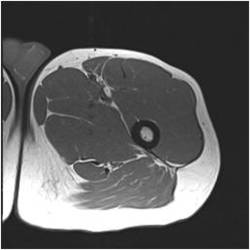

Gallery of Unlabled Radiographs from Lecture (Dr. French) - 2020

Click a thumbnail to enter the gallery display. Click the file name link at the bottom left of the gallery display to view the image at high resolution.